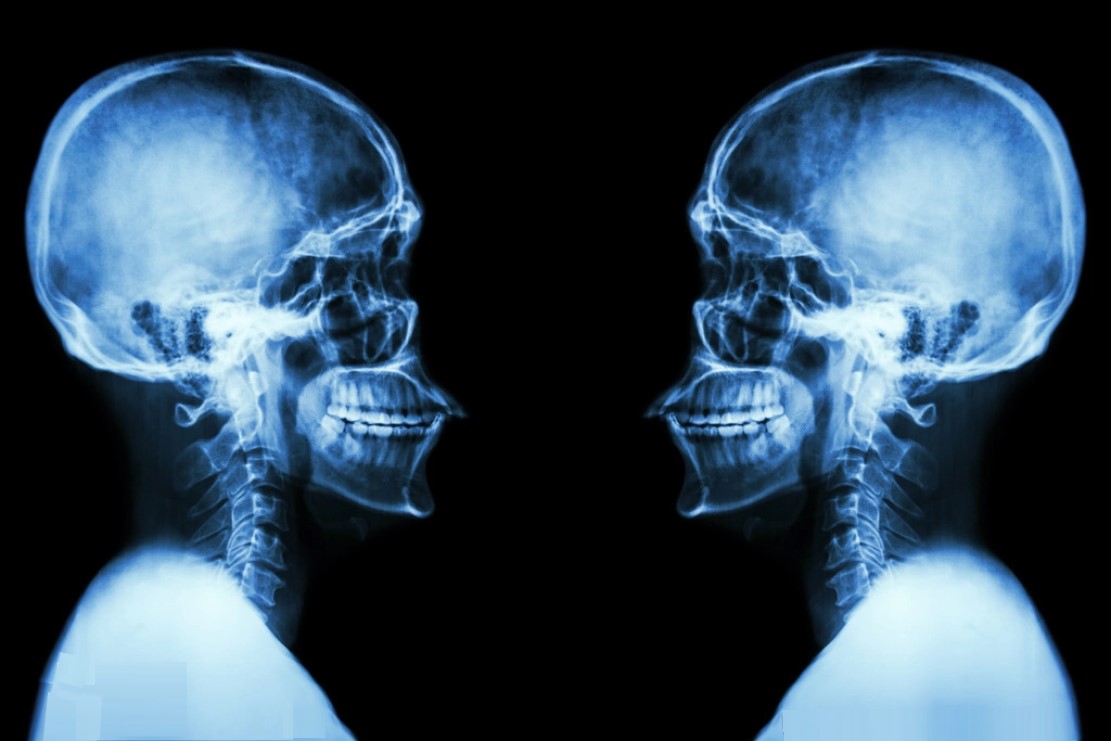

人们到医院做透视和CT检查,就是采用X射线照射,又叫X光。X射线其实就是一种光,但这种光与我们平时了解的光不同,它可以透过人体后某些物体,但眼睛却看不见。

X射线是仅次于γ射线的电磁波,波长在10纳米~0.01纳米之间,频率在3^16~3^20赫兹之间,能量为124eV~1.24MeV。这是每一个光子的能量,属于高能射线,因此穿透力很强。当X光照射人体时,一部分被人体物质吸收,大部分会从原子隙缝穿越透过。

频率越高波长越短的X光能量越大,穿透能力越强。在穿透物体的过程中,根据物体的密度和厚度,吸收不一样,因此穿越的X光就有强有弱,这样就在感光胶片中显示出被穿越物体的结构来。

当他觉得这种新发现的光已经确信无疑,已经过去了7个星期了。1895年12月22日晚上,他说服了自己的夫人来当实验对象,当他夫人将自己带有戒指地伸向荧光屏时,令人震惊而奇异的现象出现了,伦琴夫人看到一只瘦骨嶙峋的手,再仔细一看,那不是手,而是一个个骨节。

夫人不敢相信,这就是自己的手?但在影子的无名指骨节上,分明有一个戒指,与自己戒指戴的位置一点都没有偏差!伦琴夫人被自己的手吓住了,要知道那个年代还有谁看到过这种影像?只有死人的白骨才会这样。

而这是人类第一张X光照得的人体照片!伦琴异常激动地拥抱了夫人。终于证实了,这是一种前所未有的光,能够穿透肉体的光。

伦琴是个低调的人,但1896年1月23日,他在自己的研究所举行了他一生唯一一次报告会,公布了自己的发现。报告会上,伦琴请求维尔茨堡大学著名解剖学家克里克尔,伸出自己的手让他当场用X射线拍摄,克里克尔欣然同意。当拍好的干板经过显影,出现一位八十岁老人优美的手骨时,全场掌声雷动,爆发出欢呼。

最早开发出X光引用的是医学,这就是透视技术。人们通过X光照射,可以看到本应通过解剖才能看到的病变,为无数人更好地解除了病痛。当时英国著名外科医生托马斯·亨利将X射线称为“诊断史上的一个最大的里程碑”。